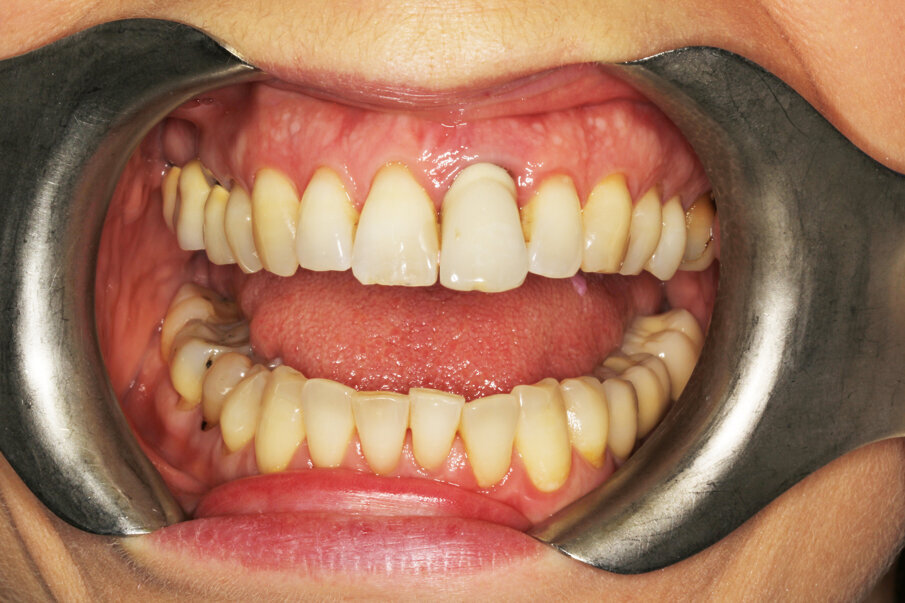

The female patient, aged 47 and a non-smoker, was in good general health. She performed regular oral hygiene and had good periodontal health. The patient experienced increasing mobility of the maxillary left central incisor and complained about compromised aesthetics due to the extrusion and progressive migration of the tooth in a buccal direction. The incisor had been treated with a crown at a preadolescent age after a violent trauma. The intraoral radiograph showed incomplete root development and evidence of a root canal therapy suggesting a strip perforation though no signs of periapical lesions were present. The shape of the crown was not symmetrical in relation to the triangular shape of the maxillary right central incisor, but had a wider and rectangular profile. Minor general gingival recession had led to the presence of a tiny inter-dental space. The marginal gingiva was reddened, and the central papilla was not symmetrical.

Probing depths were within 2 mm for both the right and left central incisors and the radiographic mesial and distal bone peaks were of a regular height.

The photographic aesthetic evaluation showed that it would be very difficult to obtain symmetry in tooth shape and have good-looking and healthy soft tissue support at the same time. The patient’s maximum smile exposed the gingival contours. In such cases, it may be wise to consider also the possibility of altering the anatomy of the contralateral tooth with, for example, a ceramic veneer and discuss outcomes with the patient before finalising the treatment plan. This can be evaluated by performing the cut/copy/flip/paste sequence in reverse (Fig. 7). Together with the patient, it was decided to start performing the best possible replacement of the maxillary left central incisor and evaluate at an advanced stage with a temporary crown on the implant and mature, conditioned tissue whether to add a veneer to the maxillary right central incisor.